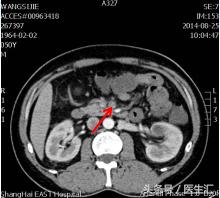

到晚上9:30的时候,患者又出现上腹部腹痛,而且腹痛呈持续性,伴恶心呕吐2次,呕吐呈非喷射状,呕吐物为胃内容物,解黄色水样便一次。夜班医生给与耐信(埃索美拉唑钠)抑酸,得舒特(匹维溴铵)解痉治疗,腹痛不能缓解。再次复查电解质+淀粉酶正常;血常规白细胞和中性粒细胞增高,其他正常。结合患者腹痛、恶心呕吐、水样便,症状很像急性胃肠炎,所以给与左氧氟沙星(左克)抗炎治疗,同时用654-2解痉等治疗。但是患者持续性腹痛没有明显缓解,第7天凌晨2:00夜班医生查体全腹部平软,但是上腹部有一点点轻压痛,无反跳痛,麦氏点无压痛,夜班医师给与654-2解痉处理,但是效果还是不满意。所以做了一个中上腹CT平扫示:肠系膜上动、静脉周围渗出性改变,建议增强扫描。

第7天凌晨2:00夜班医生查体全腹部平软,但是上腹部有一点点轻压痛,无反跳痛,麦氏点无压痛,夜班医师给与654-2解痉处理,但是效果还是不满意。所以做了一个中上腹CT平扫示:肠系膜上动、静脉周围渗出性改变,建议增强扫描。第7天早上10:00做中上腹增强CT示:肠系膜上动脉内低密度影,考虑附壁血栓形成,局部管腔重度狭窄。这个时候这个患者的诊断应该来说已经很明确了。于是请了相关科室的医生进行会诊,决定进行经皮选择性肠系膜动脉造影+肠系膜动脉溶栓术。患者溶栓导管行脉冲式注射尿激酶溶栓,患者术后24h出现便血4次,200ml/次。